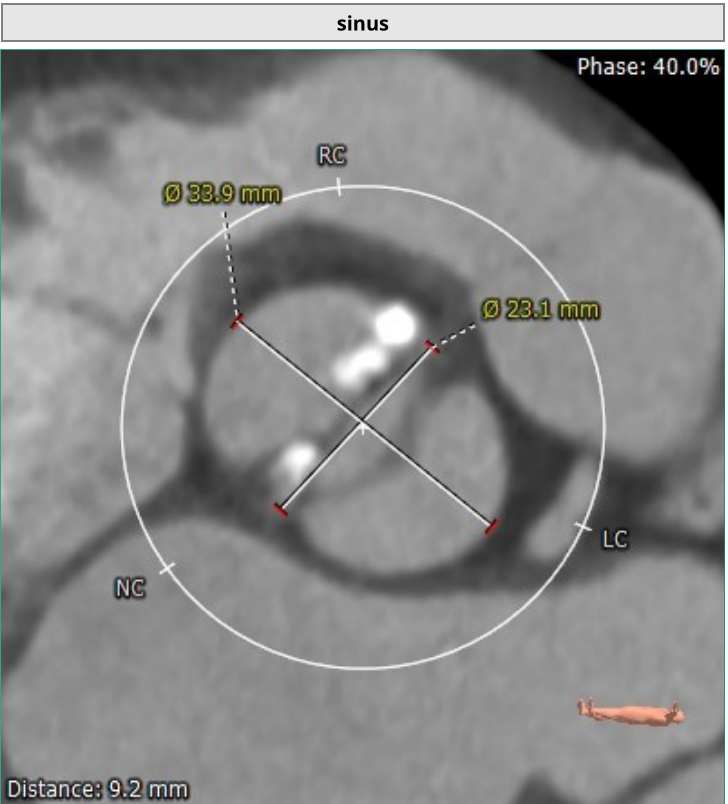

该名患者为Type 0型二叶瓣,右冠窦轻度钙化。瓣环最短径为20.0mm,最长径为27.7mm,平均瓣环直径为23.8mm。升主动脉较宽,平均直径40.5mm。左冠开口高度13.6mm,右冠开口高度16.3mm,冠脉阻塞风险低。外周血管钙化轻,入路情况较佳。FEops分析推荐匹配26mm瓣膜。

主动脉窦